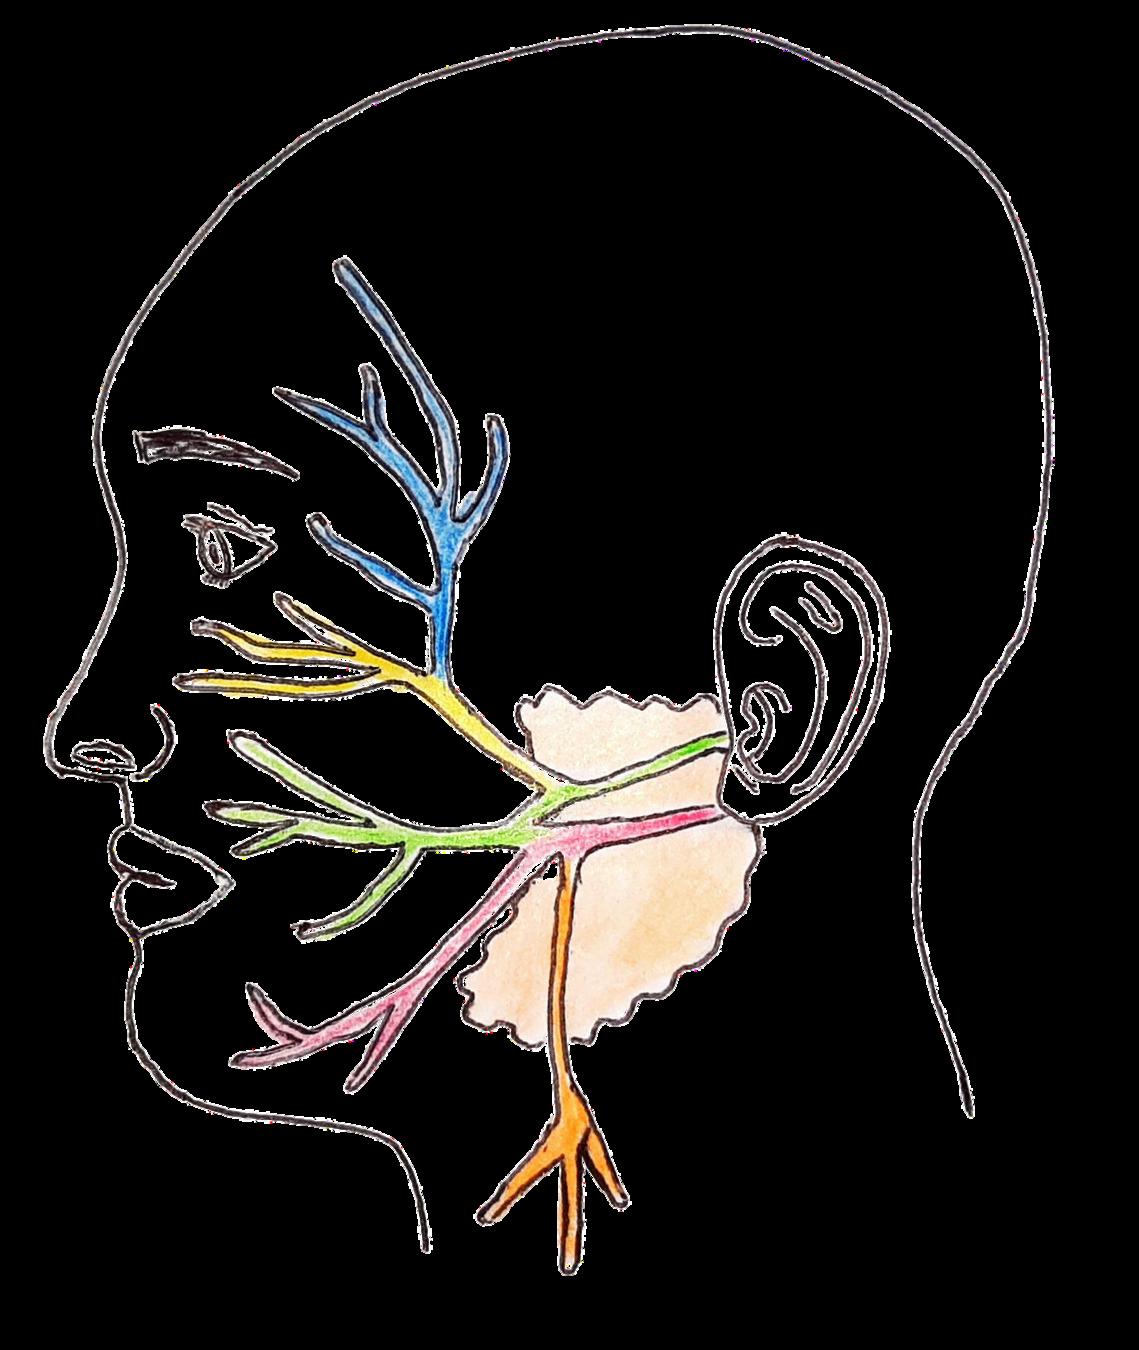

CARACTERÍSTICAS:

Lleva información entre el encéfalo y los músculos de las expresiones faciales, algunos músculos del maxilar y los músculos de los huesecillos del oído medio Recibe impulsos gustativos de los dos tercios anteriores de la lengua.

PAR)

CARACTERÍSTICAS:

Lleva los impulsos para la coordinación del equilibrio Transmite la información sobre la posición espacial de nuestra cabeza y cuerpo y, el automovimiento

NERVIO FACIAL

NERVIO

NERVIO VESTIBULAR

Temporal

Rama

GlándulaParótida

NERVIO VESTIBULAR (VIII

FACIAL (VII PAR)